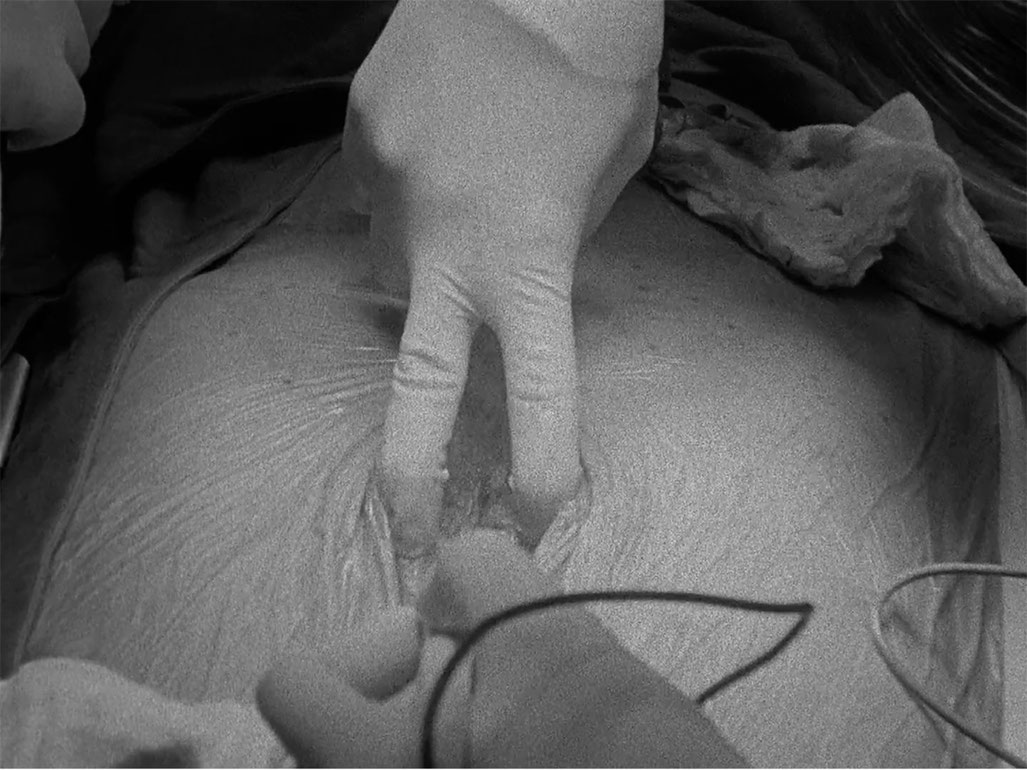

Matters of the Heart, a series of five, silent, black-and-white films of operations were shot with a 16mm Bolex film camera in the operating room: Heart, Stomach, Blood Flow, Vertebra, Eye/Hand. Two choreographies overlap: that of the surgeons and that of the intuitive-conceptual camera editing during the filming. The extremely concentrated material ends in several cases before the operation is over, rips open into white. Christina Lammer´s films require elaborate preparations: the artist and sociologist makes on site samples, sketches, and studies the time lapses with the digital Bolex. Together with all involved, she works out the concept and mutual trust: "The negotiation processes - not only with the patients who allow me to film their operations, but also with the entire hospital administration and the medical ethics commission - are, in fact, quite complex. I get along well with the patients. I ask for their consent, and give a detailed explanation of my intentions and how I handle the pictures. Since they are not personally recognizable in almost all of the operations, they gladly allow me to film in the operating room. I also visit the patients regularly as long as they are in the hospital. That is a part of it for me, and flows in the further film and video work intuitively or as experience. There is nothing uncomplicated about this form of film."(Ch.L.)

The skin as a linear border developed along with the bourgeois individual in the modern era; there were times when it was perceived as more permeable, as a porous mesh that is a potential opening. In Lammer´s films, hands covered in brightly colored gloves with shiny operating tools stake out the terrain, make contact with the fluids, tissues, bowels, and organs of the opened body - and unearth the "small, specific frissons" (W. Benjamin). Tactile qualities structure the gaze in this somatic contact zone. A precise cut, the pulsating movement of the hand in the depths of the body, sputtering blood, valiant gripping of an organ, threading hands, a tiny nerve - all of this in the fine, soft gray tones of the empathetic film material. (Madeleine Bernstorff)